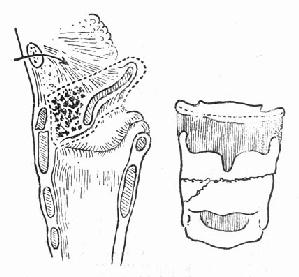

(1)急性声门上损伤:声门上损伤包括甲状软骨板上半部骨折和会厌损伤(图96-1)。有急性喉阻塞者首先行常规气管切开术,然后行前连合直接喉镜检查,注意喉水肿和喉及下咽粘膜裂伤的情况。手术包括缝合粘膜裂口并切除会厌及会厌谿之血肿组织,颈前在舌骨水平做横切口,剪断舌骨后,给行切开甲舌膜进入咽腔(图96-2)。切除会厌,会厌根部血肿组织及双侧假声带(图96-3)。用丝线缝合喉粘膜,尽量对合复位骨折的甲状软骨板,并用丝线缝合甲状软骨外板软骨膜,再缝合甲舌膜(图96-4)。逐层缝合切口。术后48h经鼻咽置入下咽部一条吸引引流管,持续引流。待喉部手术后反应消退,可试行堵管,呼吸道通畅即可拔除气管套管。

图96-1 声门上损伤

图96-2 声门上损伤手术方法 剪断舌骨,纵行切开甲舌膜。